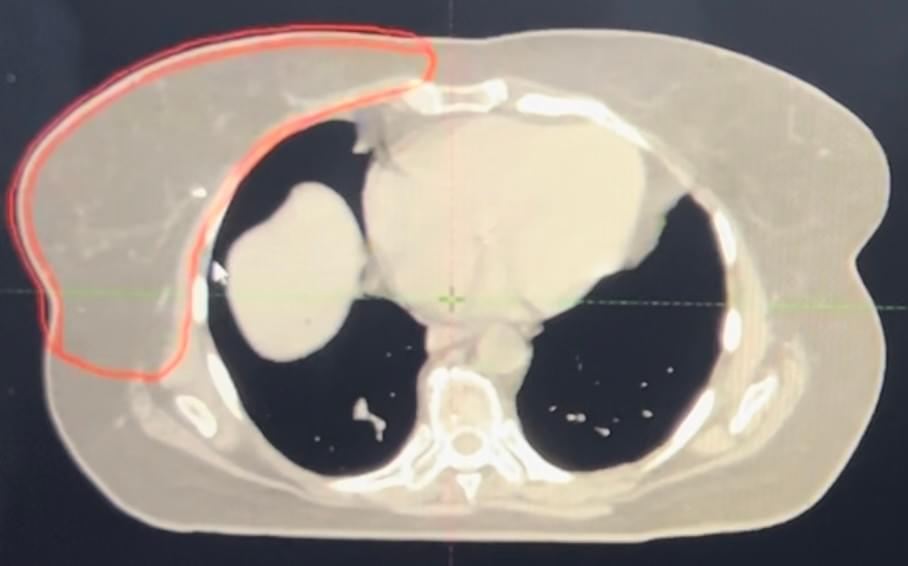

Spine Patient Optimal Radiosurgery Treatment for Symptomatic Metastatic Neoplasms (SPORTSMEN)

Phase II multicenter randomized controlled trial assessing the optimal radiation treatment [radiosurgery/stereotactic body radiation therapy (SBRT) versus conventional external beam radiation therapy (EBRT)] of symptomatic cancer that has spread to the spine for achieving pain freedom